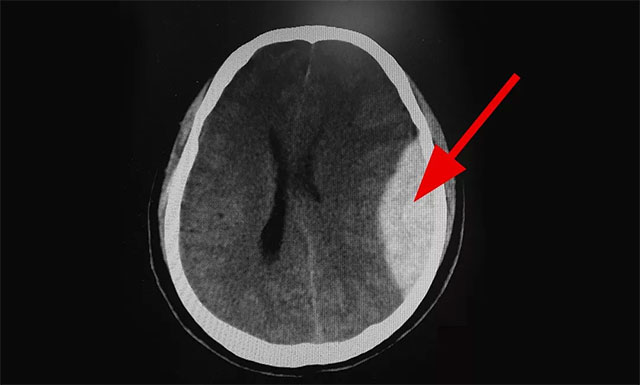

近日,上海蓝十字脑科医院急诊科就收治一名酒后的男性患者,其意识不清,并不慎摔倒,而自己却不知道,造成左侧额顶叶急性硬脑膜外血肿伴脑疝形成,情况危急,幸好抢救及时,已脱离了生命危险,之后也未留下任何后遗症。

▲ 患者出血严重,情况危急

10:01,CT检查结果显示:患者为左侧额顶叶急性硬脑膜外血肿伴脑疝形成,病情非常危急,卒中小组立即联系脑血管病区主任张琪博士,随后完善各项检查,待手术准备就绪,行左侧额顶叶急性硬脑膜外血肿清除术。